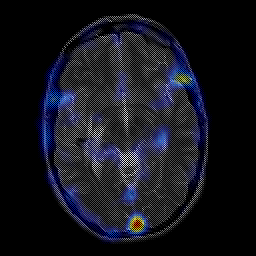

overlay -- Slice #12

[Home][Help][Clinical] Slice 12